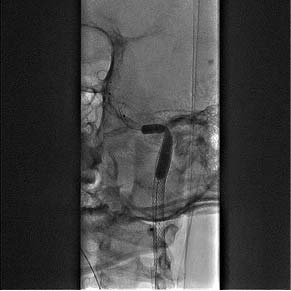

Пациент был доставлен в рентген-операционную, где с использованием правого трансфеморального доступа выполнены диагностическая каротидная ангиография и тотальная цереброангиография. На ангиограммах выявлена окклюзия левой ВСА с визуализацией диссекции в шейном отделе в виде симптома «пламени свечи» (рис. 1).

Рис. 1. Симптом «пламени свечи» в интракраниальном сегменте левой внутренней сонной артерии